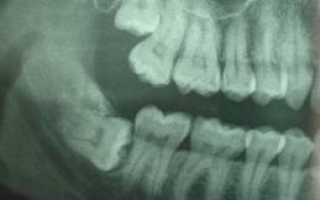

Причина возникновения болей, также кроется в особенностях прорезывания зубов мудрости. Очень часто стоматологи сталкиваются с клинической картиной, когда зуб мудрости растет горизонтально, при таком типе роста и формирования, коронковая часть восьмого зуба может толкать, задевать, и разрушать, корни соседних седьмых зубов, что неизменно приводит к приступам боли.

Горизонтальный рост зуба мудрости

Расположение зубов мудрости является препятствием не только для проведения гигиенических процедур, но и в большей степени, для проведения полного объема необходимых манипуляций при лечении. В случае, когда проведение нормального лечения затруднено, стоматолог рассматривает вопрос о необходимости удаления восьмерки. Для принятия правильного решения существует целый ряд показаний и противопоказаний к удалению зуба мудрости. После проведения рентгенографии, взвесив все преимущества и недостатки вашего зуба, специалист либо дает направление на удаление, либо продолжает проведение максимально возможной терапии.